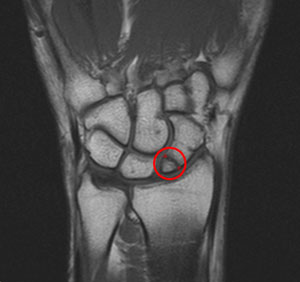

The Capitate had turned on its horizontal axis and the upper portion was now 'sticking up', thereby irritating the ligaments binding it as well as the extensor tendon of the little finger which passes over it. See the diagram below: the black line is the horizontal axis of the Capitate. The red area ( illustrated left ) was the centre of irritation.